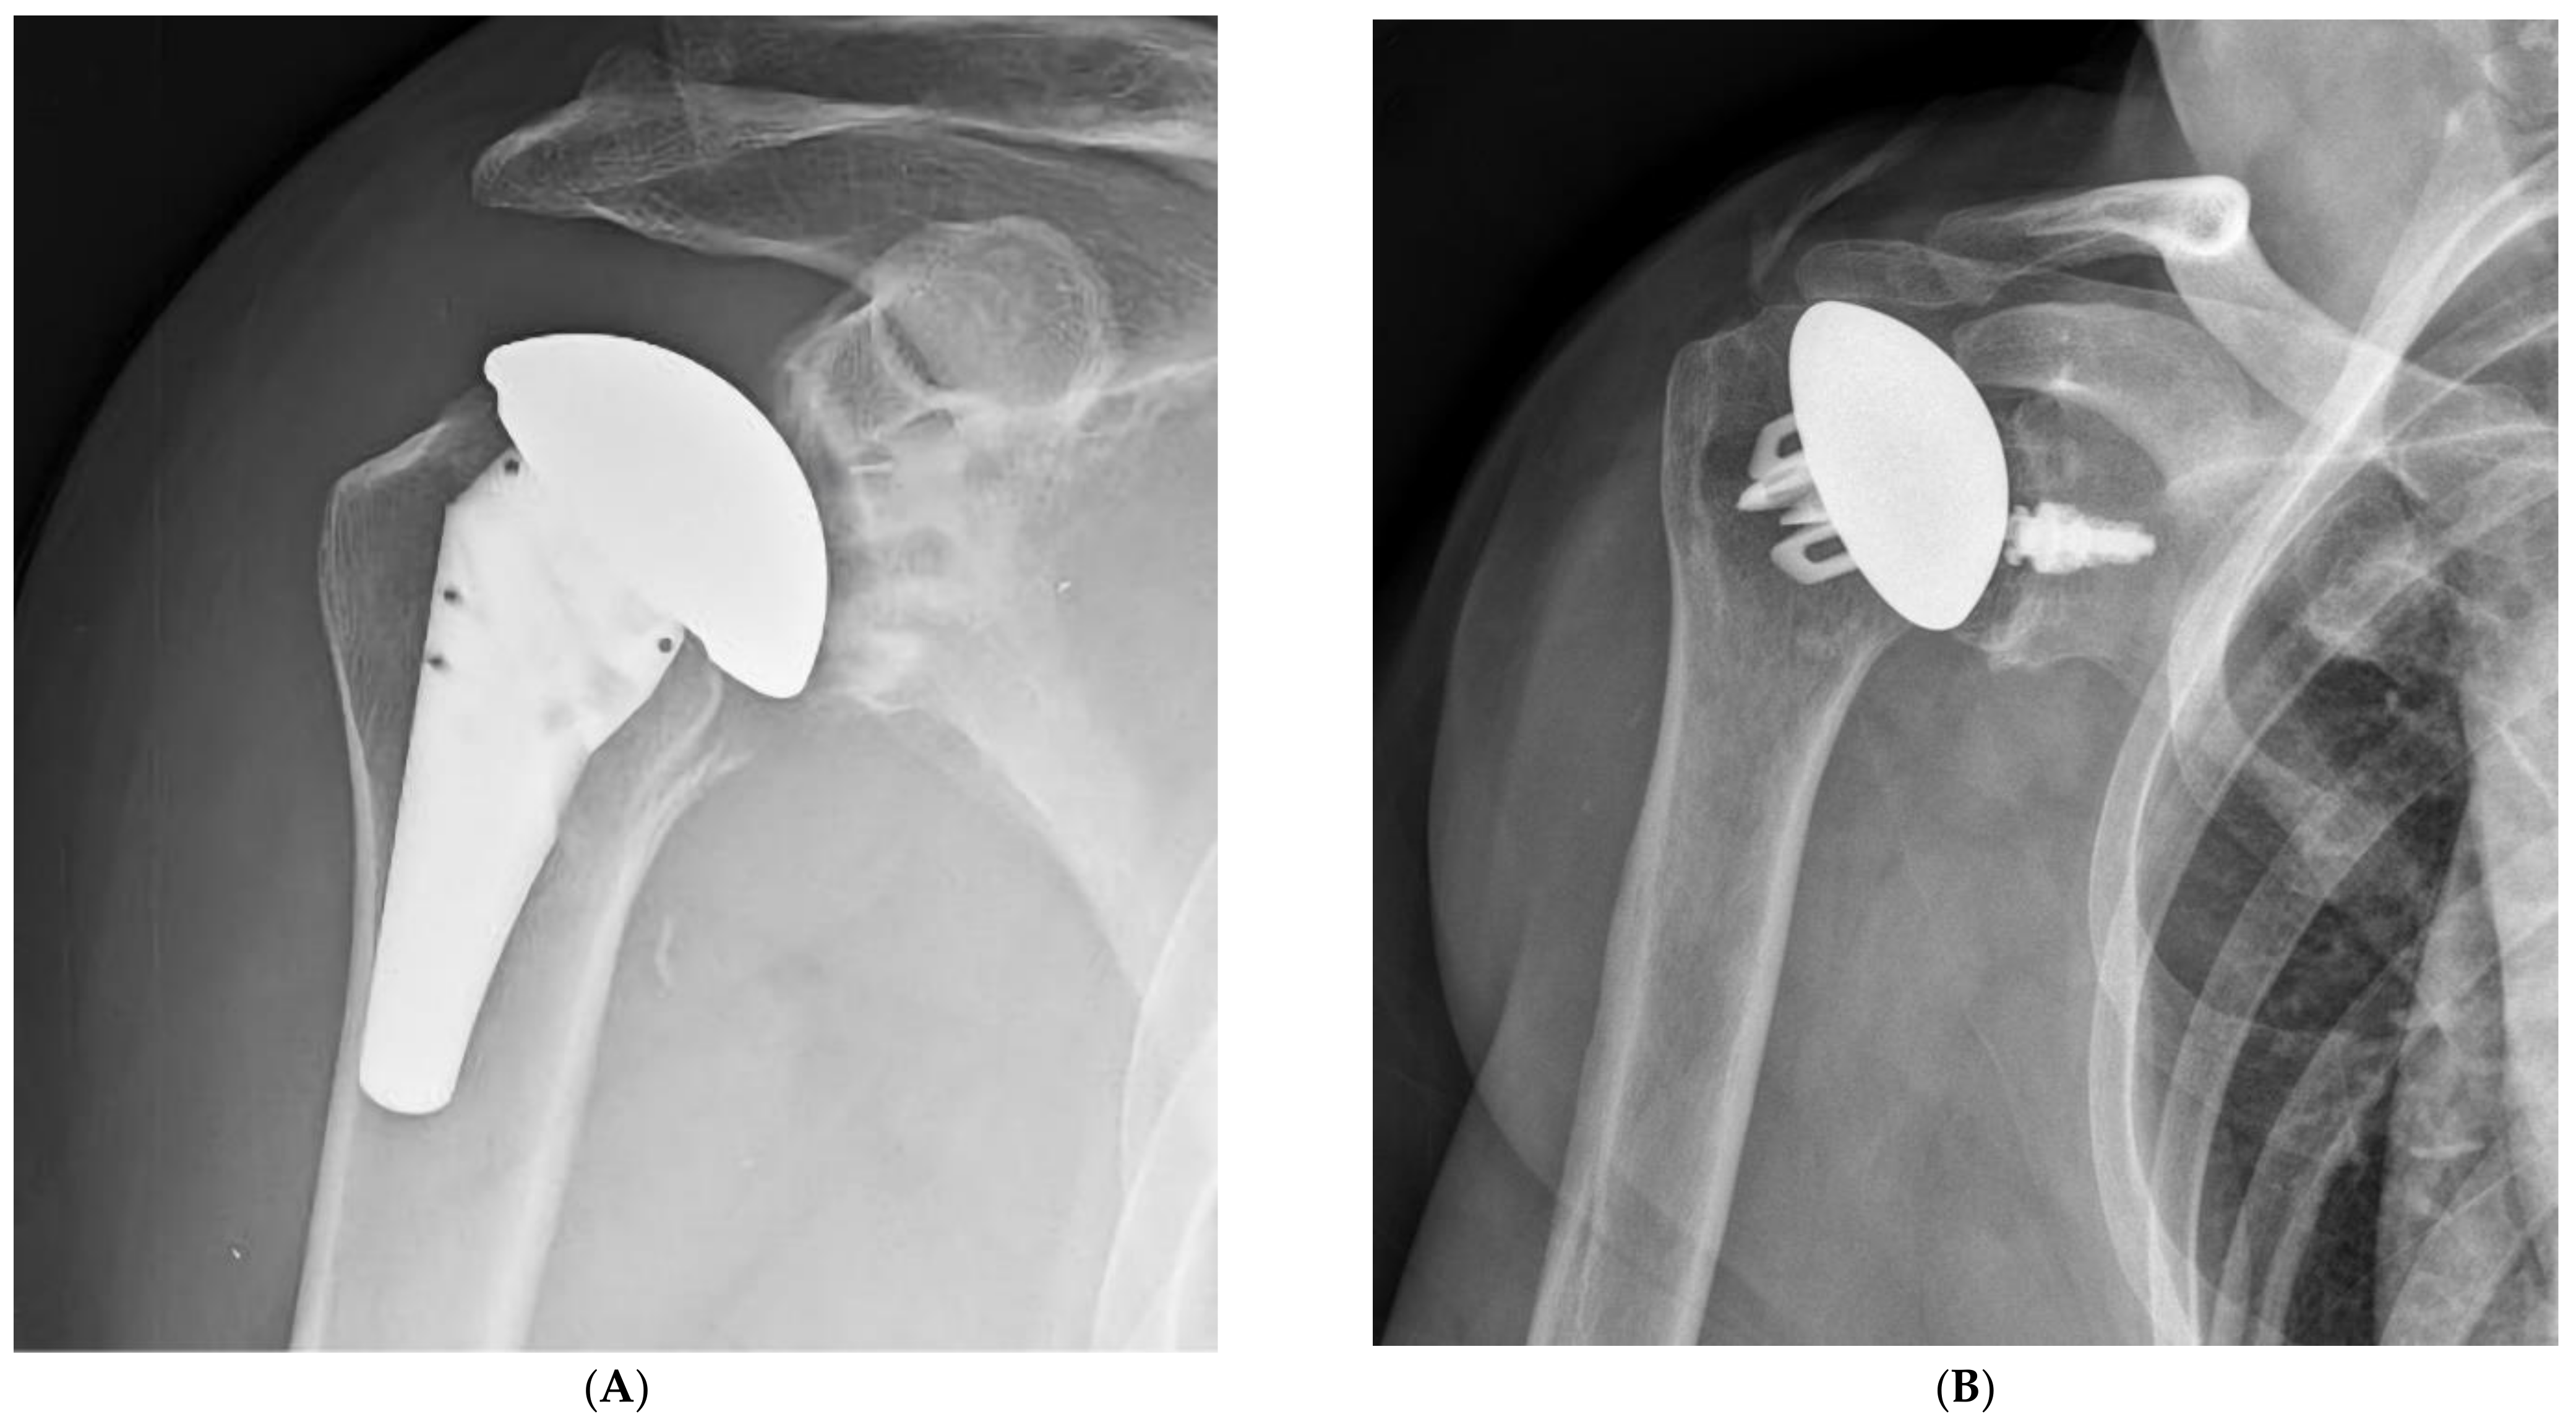

Stems that do not engage the cylindrical portion of the endosteal canal can easily be misaligned. Excessive valgus or varus will lead to a poor humeral head position in anatomic arthroplasty. Similarly, poor alignment can lead to a reverse polyethylene that is excessively horizontal with an increased risk of notching, or to a more vertical polyethylene that may facilitate dislocation. Certain short stems have been designed with just enough length to avoid malalignment [17]. Stemless prostheses are also at risk for malalignment (Figure 1). As such, care must be taken to optimize the humeral head cut to minimize the chances of malalignment with ultrashort stem and stemless prostheses.

Figure 1.

Ultrashort stems (A) and stemless prostheses (B) are at increased risk for malalignment.